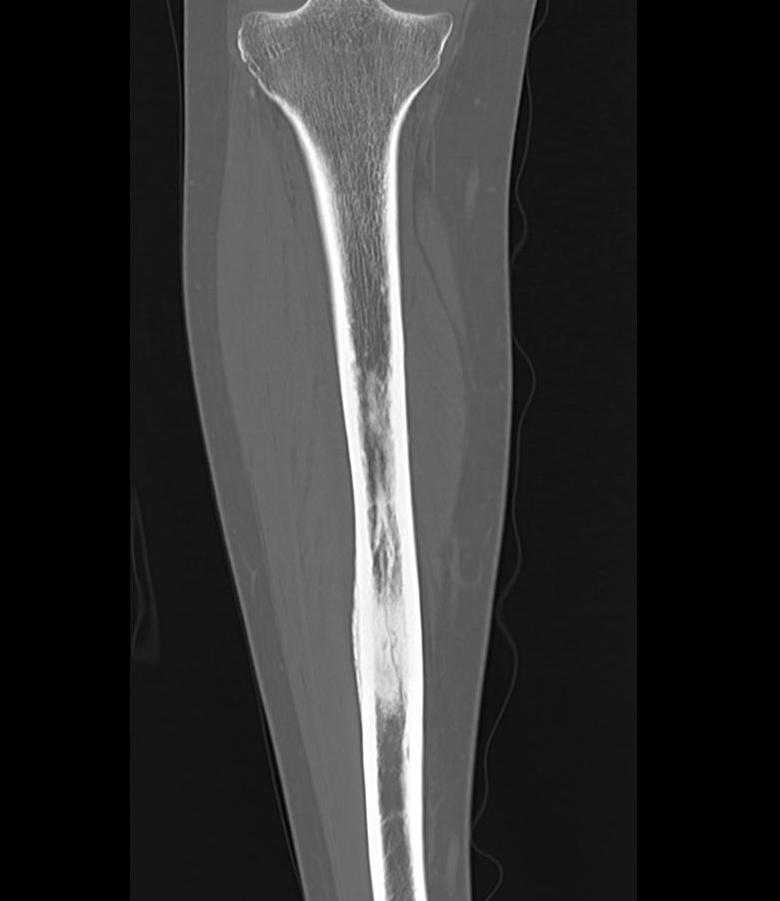

Tibia and fibular

Tibia: direct medial approach directly onto bone

2. Subtrochanteric / femoral shaft

- lateral approach

- aim anterior or posterior to lateral intermuscular septum depending on compartment